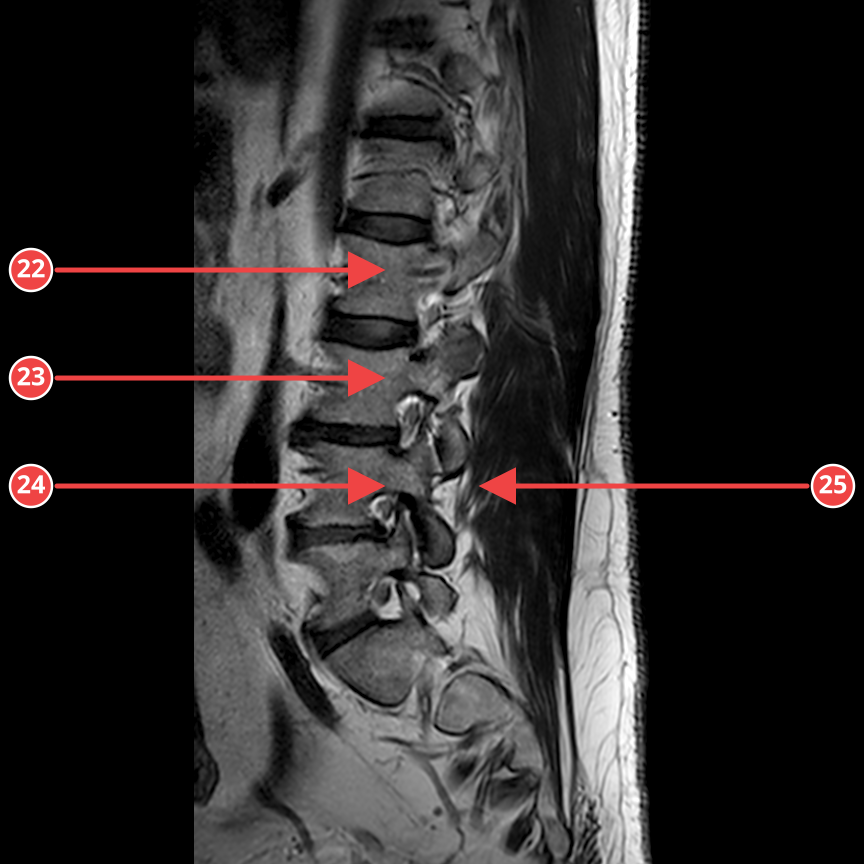

IMG-0002-00014.dcmT2_SAG

Сагиттальная T2-взвешенная последовательность пояснично-крестцового отдела. Видна центральная грыжа L5-S1 с компрессией дурального мешка и небольшая протрузия L4-L5. Остальные диски в пределах возрастной нормы.

Аномалии

- [1] Грыжа диска L5-S1 — high — Центральная грыжа с компрессией дурального мешка, размер до 5 мм. уверенность 85%

- [2] Протрузия диска L4-L5 — medium — Циркулярная протрузия, выраженная центрально, до 3 мм. уверенность 82%

- [3] Дегенерация диска L3-L4 — low — Снижение сигнала в T2W, начальные признаки. уверенность 75%